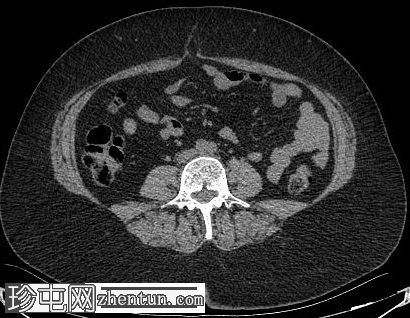

轴位增强扫描

动脉期

肝脏内可见多发边界清晰的脂肪结节状病变,最大病变位于肝脏VII段,直径15 mm

双肾可见多发脂肪肿块,右肾最大病变直径达45 mm,左肾最大病变直径20 mm

心肌脂肪组织

椎体可见小的硬化性骨病变

胆囊腔内可见多发结石,诊断为胆石症

可见小的脐疝,内含腹膜前脂肪

肾血管平滑肌脂肪瘤是结节性硬化症最常见的腹部表现,通常为多发性、双侧性,且体积大于散发性病变。血管平滑肌脂肪瘤。肝脏血管平滑肌脂肪瘤虽然不常见,但却是公认的肾外表现,其影像学特征与肾脏血管平滑肌脂肪瘤相似,包括CT扫描可见肉眼可见的脂肪,这使得诊断成为可能,且无需侵入性检查。

肾脏和肝脏中富含脂肪的血管平滑肌脂肪瘤可能仅有轻微或无明显的对比增强,仅表现为衰减值的轻微升高,反映血管和间质成分的增强。这些病灶内肉眼可见的脂肪具有高度特异性,有助于将血管平滑肌脂肪瘤与其他肾脏和肝脏肿瘤区分开来。

此外,多发性小骨硬化性病变是结节性硬化症的常见骨骼表现,在适当的临床背景下,不应误诊为成骨性转移。

识别包括多发性含脂肪肾血管和肝血管平滑肌脂肪瘤以及多灶性骨硬化病变在内的影像学表现至关重要,因为这有助于确诊结节性硬化症,并避免不必要的活检或其他侵入性检查。